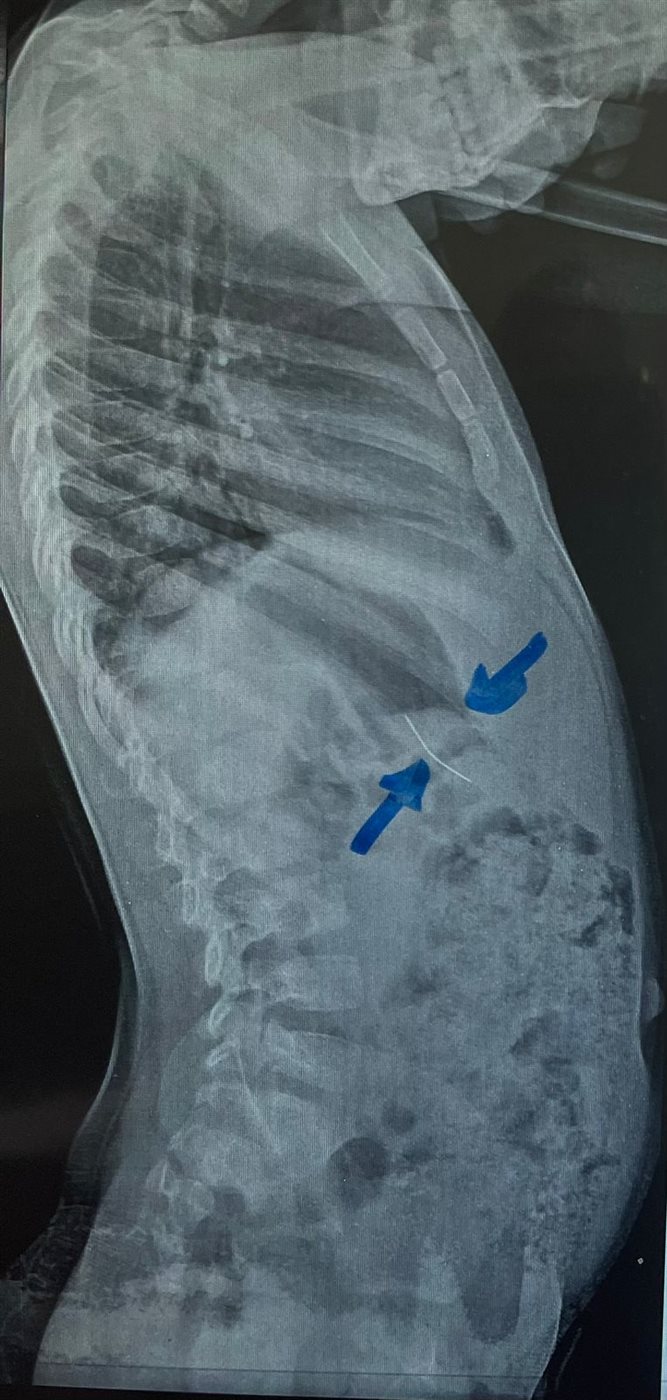

نجح فريق طبي من وحدة أمراض الجهاز الهضمي والكبد ومناظير الأطفال بقسم طب الأطفال بمستشفى سوهاج الجامعي في إجراء تدخل دقيق لاستخراج دبوس من معدة صغير يبلغ من العمر 4 سنوات، باستخدام منظار معدة خاص بالأطفال، دون حدوث أي مضاعفات، وغادر الطفل المستشفى بعد ثلاث ساعات فقط من الإجراء، وهو في حالة صحية جيدة.

وأكد الدكتور أحمد كمال، المدير التنفيذي للمستشفيات الجامعية، أن التعامل مع الحالة تم بسرعة وكفاءة، حيث تمكن الفريق الطبي من استخدام المنظار الخاص بالأطفال لاستخراج الدبوس دون أي تدخل جراحي، مما ساهم في خروج الطفل من المستشفى في نفس اليوم بحالة ممتازة.